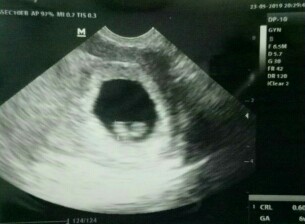

Bun,usia 6w gambar usg nya kygini normal ga sih Bun?? Tadi dokternya bilang, ga berkembang masa?? Disuruh balik lagi seminggu selanjutnya untuk di usg lagi

Kecepetan usg bun kebanyakan klo usg dibawah 12w dibilang gk berkembang

saya 6W kaya begini bun, usg transvaginal bun, coba aja bun usg lagiii

Wajar bun ,saya 5 minggu 4 hari juga kya gitu ada kantung rahimnya bun

Mnirutku normal bun usia segitu msih keliatan kantong hamilnya doang

Sy 8 weeks baru keliatan bun Sbr ya Coba dokter lain ja Semngat bub

Baca lagiKlo 6minggu wajar kyaknya bund segitu.... cb usg lg nunggu 2 minggu

Normal. Nanti minggu ke 8 insyaAllah keliatan. Saya dulu juga gitu.